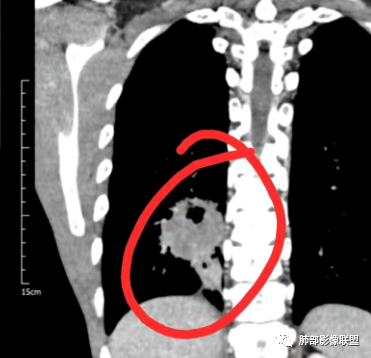

右肺下叶背段实变影,宽基底与胸膜相连,边缘毛糙,内部可见空洞影,空洞壁光滑,内部可见坏死,近端支气管显示不清,远端胸膜下间隙可见,青年男性,考虑结核,鉴别NTM,鳞癌

青年男性,呼吸道症状起病,右肺下叶背段肉芽肿样变,边缘分叶,胸膜糊墙,略牵拉,内部密度不均,空洞无物,壁整,支气管通畅,卫星灶,玫瑰结状小叶中心性结节及少量树芽;中度强化,湖泊样坏死,内部无完整血管影:结核可能性、鉴别:坏死性支原体肺炎、鳞癌。

有晕征,第一感觉像是感染类病变,仔细看下叶支气管不通畅,感觉有阻塞,先考虑感染类病变,肺链?隐球?毛霉曲霉?TB?NTM?鉴别诊断肉瘤类,肉瘤样癌,类癌。

青年,咳嗦,指标基本正常,右肺下叶不规则软组织密度影,密度不均,有坏死,小空洞,宽基底与胸膜相连,支气管觉得通畅,考虑感染,鉴别结核

35岁男性患者,病史及实验室检查无免疫受损相关依据,无感染毒血症状,炎症指标CRP、降钙素原、血沉均正常,曲霉抗原阴性;CT提示右下背段肿块影,边缘膨隆,有分叶及短毛刺,偏心空洞,增强扫描提示不均匀强化,有坏死,考虑:1.腺癌 2.隐球

中年男性,咳嗽2月余,pct正常,首先排除普通肺炎。右下背段肿块,边缘毛糙,浅分叶,与胸膜宽基底相连,有坏死(无液平,为凝固性坏死,不考虑脓肿),常规考虑结核隐球菌,鉴别恶性肿瘤

青年男性患者,间断咳嗽、少量黄白痰2月,胸部CT:右肺下叶后基底段类圆形病灶,边界清楚,周围磨玻璃,内部有空洞形成,空洞干净,考虑炎性病变,脓肿,隐球,结核,鉴别鳞癌

右肺下叶肿块,分叶,近端支气管部分堵塞,部分沿壁厚,沼泽样强化,可见空洞,邻近胸膜少量积液,膈肌牵拉,考虑肿瘤,鳞癌?鉴别NTM

青年男性,慢性病程,右肺下叶团块影,形态不规则,内见空洞,壁厚薄不均,不均匀轻度强化。考虑恶性,肺癌,肿标中角蛋白19增高,倾向于鳞癌,鉴别结核。

中年男性,有咳嗽咳痰病史俩月,亚急性病程,炎性指标不高,右肺下叶后基底段近胸膜下不规则肿块,边缘膨隆毛糙,支气管近端阻塞,内有厚壁空洞,无液平,洞壁不均匀强化,周围支气管壁厚,远端有点片影,考虑鳞癌可能性大,鉴别肺脓肿和肺结核。但是血沉不快,crp不高,有点不大符合炎性。